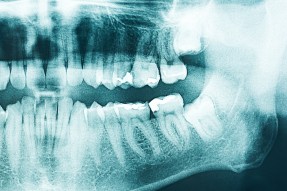

You never know when fate turns against you. For me, December 11th was my doomsday. I had an appointment with a dental surgeon for a regular apicoectomy, but things got more complicated as the infection had largely spread to the surrounding jaw bone and sinus, with one molar practically popping out of my jaw as soon as my gum was cut open. There I was, locally anaesthetized, lying with the surgeon’s tools and fingers stuck in my mouth, when the curse was laid on me – “Shit”. When you suddenly hear your doctor utter the infamous word, you know you’re screwed – as is your bank account! Only one thing is sure now: your savings are long gone and there’ll be no food, no sport, no fun, no life for you for the next few weeks! 😮

Secondly – you accept. What we dwell on expands, so let’s stop ruminating. My jaw won’t grow again overnight. My sinus is punctured. Healing takes time. Bye bye, my next workouts! So long, Sonny boy! Three-four weeks of recovery. Basta. No discussion.